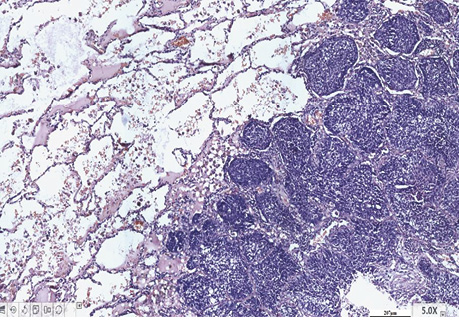

Так, у гістологічних препаратах залозистої карциноми (рис. 1, 2) різного ступеня диференціювання у 2 (13,3%) хворих установлений аденосквамозний тип РЛ. За макроскопічними даними у 2 (13,3%) хворих пухлинні вузли «зливалися» між собою, тобто не мали чітких периферичних контурів, ще у двох (13,3%) — визначався беззаперечний дифузний ріст залозистого РЛ. Крім того, в усіх гістологічних препаратах 15 хворих визначені ділянки бронхіолоальвеолярного типу РЛ. Імуногістохімічні дослідження з моноклональними антитілами (Кі-67 і PCNA) дозволили підтвердити початок росту НДКРЛ від базальної мембрани (рис. 3, 4).

Рис. 1. Залозистий рак. Характерна гістологічна структура в альвеолах і поза ними. Гістологічний препарат, гематоксилін і еозин, ×200